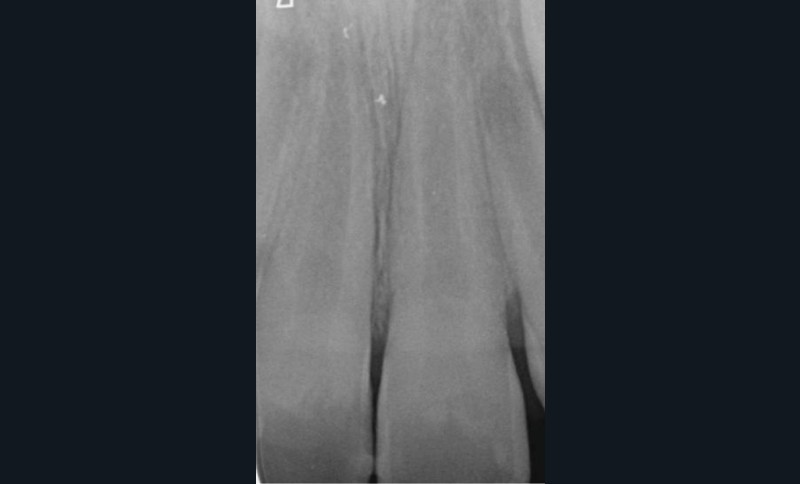

Les résorptions radiculaires inflammatoires externes surviennent après un traumatisme sévère comme une avulsion (fig. 1) ou une luxation [3], où la couche protectrice de précément et le parodonte sont altérés. Ces traumatismes peuvent provoquer une compression tissulaire au niveau du ligament parodontal, induisant des lésions vasculaires, une hypoxie et une perte d’intégrité du cément. Si la dent est restée vivante alors, un processus de réparation se met en place avec l’apposition d’un nouveau cément et d’une nouvelle attache. En revanche, si la dent venait à se nécroser, alors les stimuli pro inflammatoires résultant de l’activité des bactéries au sein du canal vont diffuser à travers les tubuli dentinaires et rejoindre les zones de résorption externe, et ainsi vont aggraver le processus résorptif qui est déjà actif [4].

Les RREI se manifestent par des signes de parodontite apicale : douleur, gonflement, sensibilité à la percussion ou à la palpation, fistule ou dyschromie de la couronne. En général, la dent affectée présente une réponse négative aux tests de sensibilité pulpaire [5]. L’examen radiographique montre des zones radioclaires irrégulières (aspect déchiqueté) autour de la racine lorsque la résorption est active. Le canal radiculaire reste visible et bien identifiable. Dans les cas avancés de résorption, la racine peut être complètement résorbée. Un examen 3D (CBCT : Cone Beam Computed Tomography) est recommandé pour aider au diagnostic et à la prise en charge de la RREI qui, cliniquement, semble traitable [6].